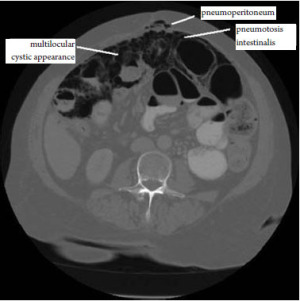

A case of bmpm presenting as pneumoperitoneum and pneumotosis intestinalis is described. To accurately diagnose benign multicystic mesothelioma a medical professional must take a biopsy of the patient's infected tissue. J med case rep 6 (1): Case report and review of the literature. In our case report, the lesion was solitary and situated in the left abdomen.

Benign multicystic peritoneal mesothelioma (bmpm) is a rare cystic mesothelial lesion that occurs predominantly in reproductive aged women. Peritoneal mesothelial cysts (pmc) are a clinical dilemma because of their true pathogenic nature. Peritoneal mesothelioma should be differentiated from multicystic peritoneal mesothelioma (mcpm) which is a benign, multicystic abdominal tumor such as cystic lymphangioma, endometriosis, cystic adenomatoid tumor, pseudomyxoma peritonei, and malignant peritoneal mesothelioma. A case of bmpm presenting as pneumoperitoneum and pneumotosis intestinalis is described. Benign multicystic peritoneal mesothelioma (bmpm) is a rare peritoneal lesion that commonly presents as lower abdominal pain, palpable mass, or both.